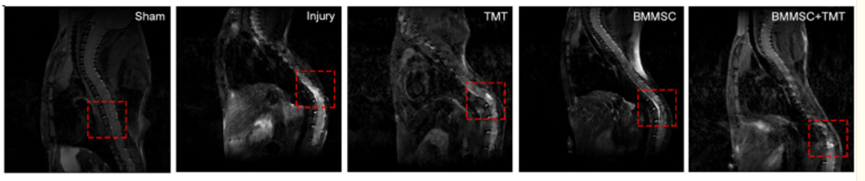

有研究表示,間充質(zhì)干細胞移植可以有效減輕脊髓損傷的程度,有利于機體的恢復(fù)。研究發(fā)現(xiàn),當(dāng)使用8周的間充質(zhì)干細胞治療之后,同樣病患的脊髓損傷程度比不接受干細胞療法的病患要輕得多[4]。